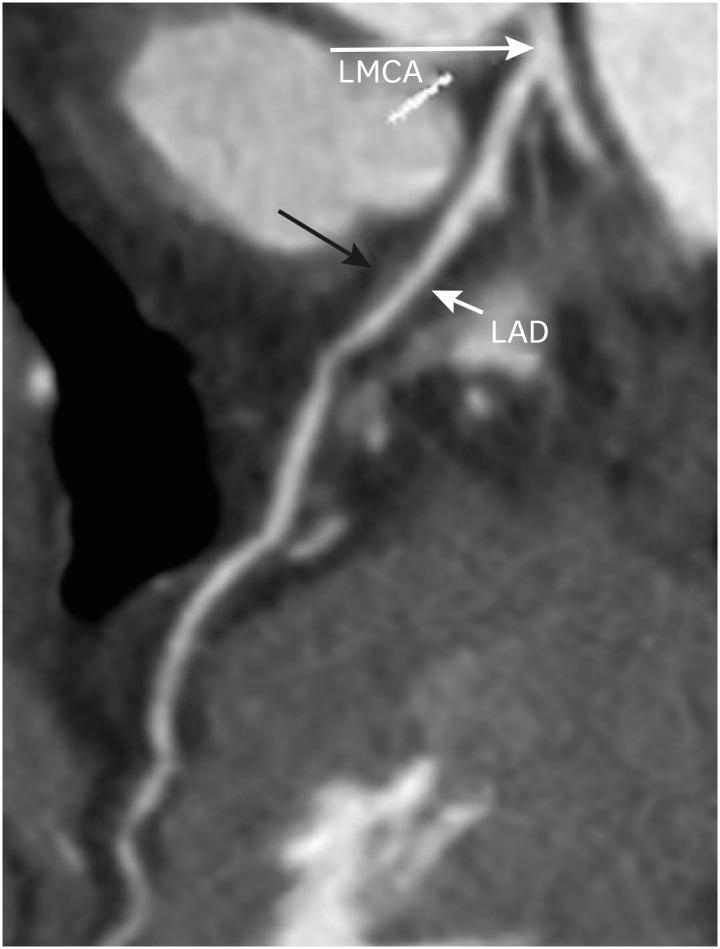

冠状动脉疾病报告与数据系统:全面综述。

Coronary Artery Disease Reporting and Data System: A Comprehensive Review.

The Coronary Artery Disease Reporting and Data System (CAD-RADS) is a standardized reporting method for coronary computed tomography angiography (CCTA). It summarizes the findings of CCTA in 6 categories ranging from CAD-RADS 0 (complete absence of coronary artery disease) to CAD-RADS 5 (total occlusion of at least one vessel). It is applied on per patient basis for the highest grade of the stenotic lesion. The CAD-RADS also provides category-specific treatment recommendations, helping patient management. The main objectives of the CAD-RADS are to improve the consistency in reporting, facilitate the communication between interpreting and referring clinicians, recommend the best course of patient management, and produce consistent data for quality improvement, research and education. However, CAD-RADS has many limitations, resulting into the misclassification of the observed findings, misinterpretation of the final category, and misguidance for the treatment based upon the single score. In this review, the authors discuss the CAD-RADS categories and modifiers, along with the strengths and limitations of this new classification system.

冠状动脉疾病报告与数据系统(CAD-RADS)是一种用于冠状动脉计算机断层扫描血管造影(CCTA)的标准化报告方法。它将CCTA的结果总结为6类,范围从CAD-RADS 0(完全不存在冠状动脉疾病)到CAD-RADS 5(至少一根血管完全闭塞)。它针对每位患者应用于狭窄病变的最高等级。CAD-RADS还提供特定类别的治疗建议,有助于患者管理。CAD-RADS的主要目标是提高报告的一致性,促进解读医生与转诊医生之间的沟通,推荐最佳的患者管理方案,并产生用于质量改进、研究和教育的一致数据。然而,CAD-RADS有许多局限性,导致观察结果的错误分类、最终类别的错误解读以及基于单一分数的治疗误导。在本综述中,作者讨论了CAD-RADS类别和修饰符,以及这个新分类系统的优点和局限性。